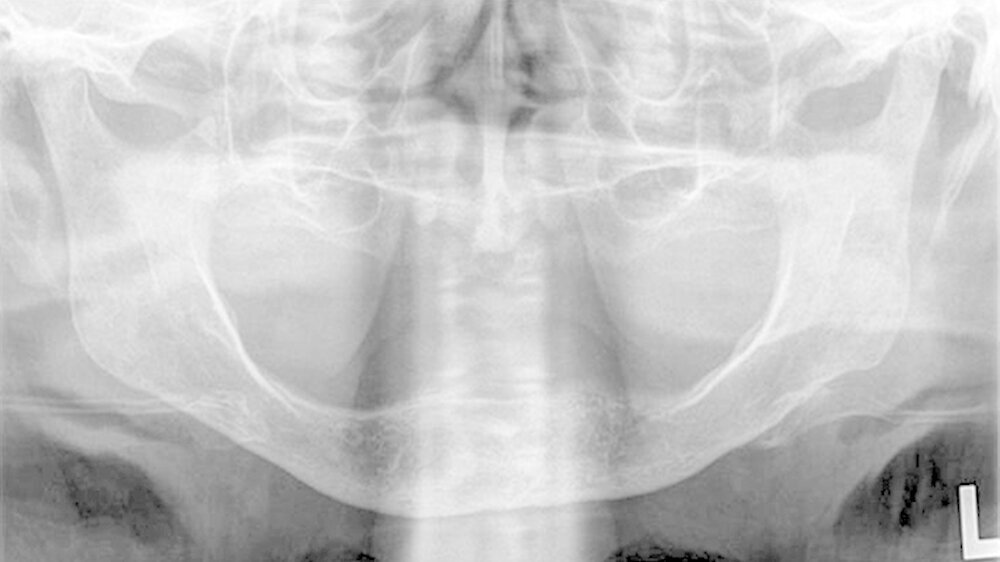

Die klinische Untersuchung zeigte eine überwärmte, schmerzhafte Schwellung präauriculär links und eine stark eingeschränkte Mundöffnung bei zahnlosem Kiefer. Das angefertigte Orthopantomogramm und die Schädelaufnahme in posterior-anteriorer Projektion gaben keinen eindeutigen Hinweis auf Pathologien im Bereich des linken Kiefergelenks, mit denen die ausgeprägten Beschwerden der Patientin hätten erklärt werden können.

Es war lediglich ein stark verschmälerter Gelenkspalt im Bereich des linken Kiefergelenks erkennbar, woraufhin eine Computertomografie des Unterkiefers durchgeführt wurde (Abbildungen 1 und 2). Dabei zeigten sich eine Deformierung des linken Kiefergelenksköpfchens mit Unregelmäßigkeiten der Kortikalis sowie eine Fremdkörpereinlagerung (freie Gelenkkörperchen) im Bereich des Gelenkspalts (Abbildungen 3 und 4).